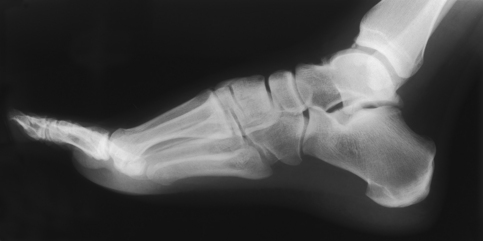

The lateral (mediolateral) projection is routinely used in most radiology departments because it is the most comfortable position for the patient to assume.

• Elevate the patient’s knee enough to place the patella perpendicular to the horizontal plane, and adjust a sandbag support under the knee.

• Adjust the foot to place the plantar surface of the forefoot perpendicular to the IR (Fig. 6-50).

• Center the IR to the midfoot, and adjust it so that its long axis is parallel with the long axis of the foot.

• Dorsiflex the foot to form a 90-degree angle with the lower leg.

Structures shown: The resulting image shows the entire foot in profile, the ankle joint, and the distal ends of the tibia and fibula (Figs. 6-51 and 6-52).